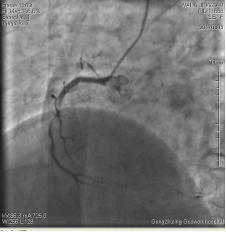

3月3日14時(shí)30分:經(jīng)右橈動(dòng)脈行冠脈造影見:左主干未見明顯異常,TIMI血流3級(jí),前降支開口正常,近中段20%狹窄,TIMI血流3級(jí);回旋支開口正常,中遠(yuǎn)段75%狹窄,TIMI血流3級(jí)。右冠狀動(dòng)脈開口正常,中段長病變,最重99%狹窄, TIMI血流3級(jí)。

圖1 回旋支遠(yuǎn)段70%狹窄 圖2 右冠脈中段99%狹窄